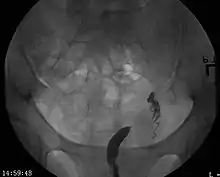

- Los dos conductos Mullerianos están fusionados pero la separación entre ellos todavía está presente, separando el sistema en dos partes. Con un septum completo la vagina, el cérvix y el útero se pueden separar. Usualmente el septum afecta solo la parte craneal del útero. Un septum uterino es la malformación uterina más común y la causa de muchos abortos espontáneos. Es diagnosticado por técnicas de imágenes médicas como ecografía o resonancias magnéticas (MRI por sus siglas en inglés). La resonancia magnética (MRI) es considerada la mejor herramienta de diagnóstico debido a sus capacidades de multiplanos así como también su habilidad de evaluar el contorno uterino, zona nodal, y otras anatomías pélvicas. Un histerosalpingograma no es considerado de utilidad debido a su inhabilidad para evaluar el contorno exterior del útero y distinguir entre un bicornio y un útero particionado.

Aparte del examen físico, el doctor necesitará tomar imágenes para determinar las características de la malformación: Ultrasonografía ginecológica, resonancia magnética (MRI) pélvica o histerosalpingografía. Un histerosalpingograma no es considerado de utilidad debido a su inhabilidad para evaluar el contorno exterior del útero y distinguir entre un bicornio y un útero particionado. Adicionalmente una laparoscopia y/o histeroscopia pueden ser recetados. En algunos pacientes el desarrollo vaginal puede ser afectado. Al contrario de lo que pudiera pensarse, esta "malformación" no representa incomodidad alguna para la persona que la presente.